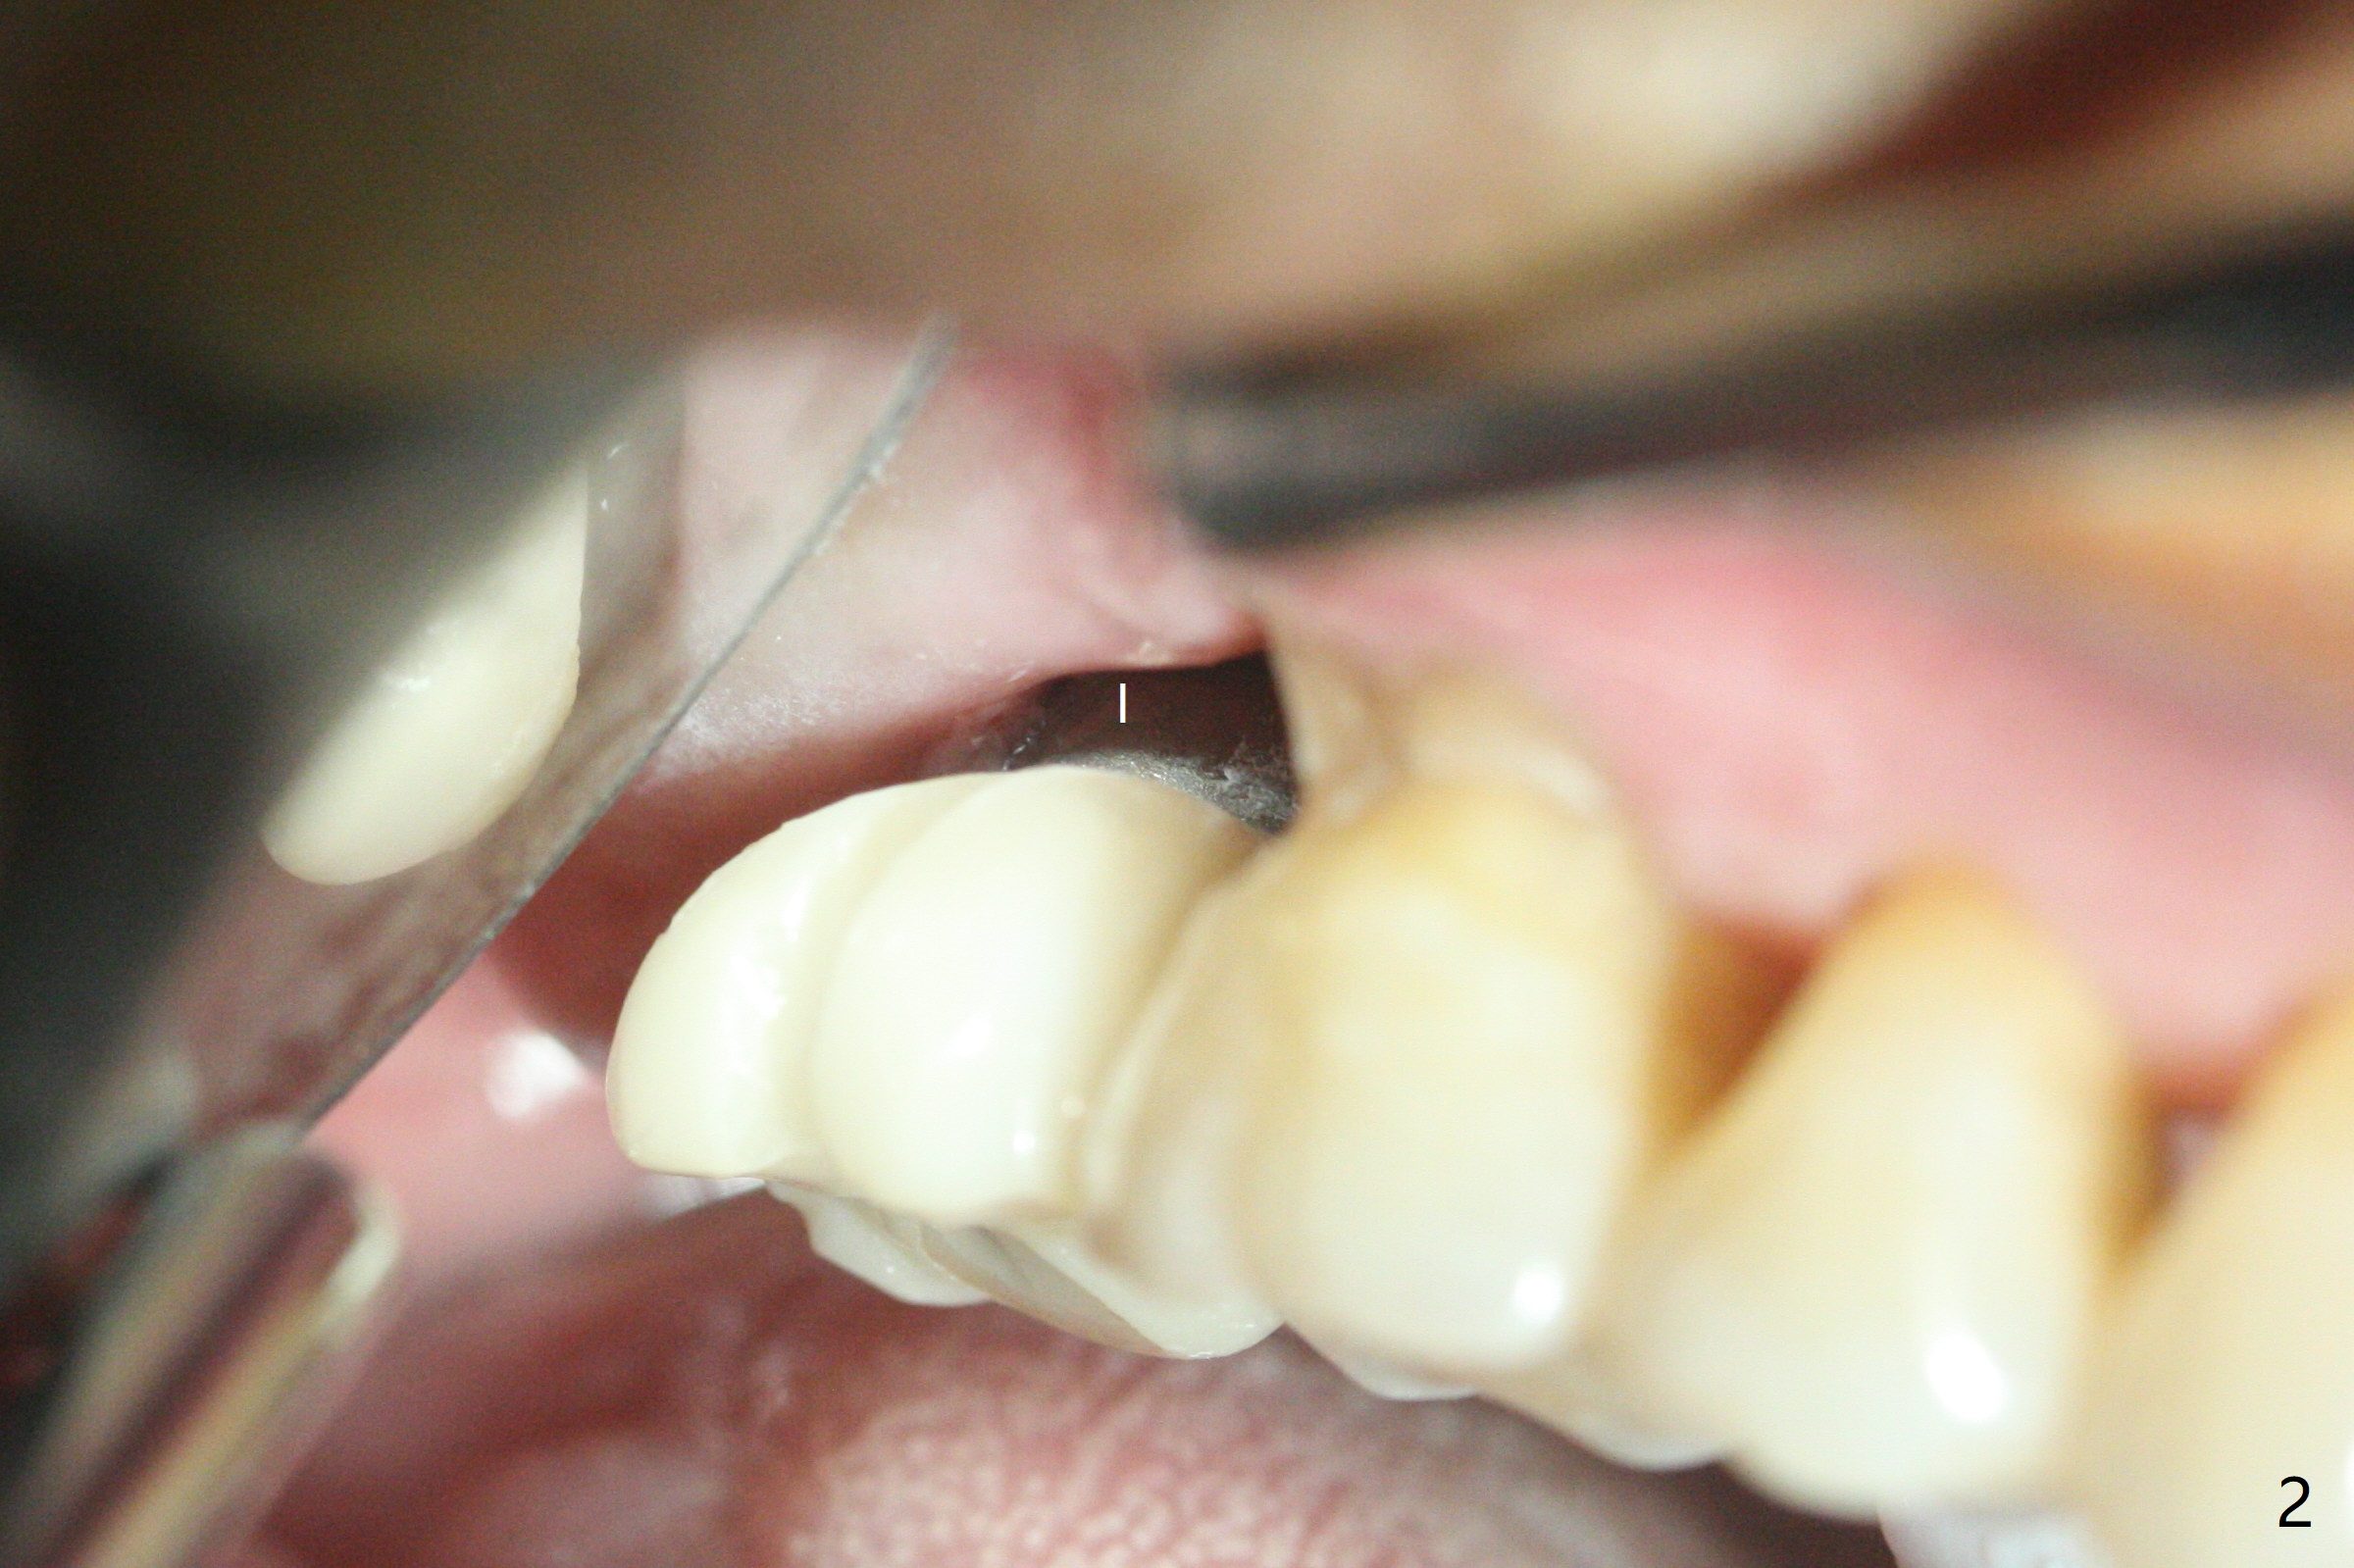

50岁男,二型糖尿病,对常用糖尿病药物无效,使用胰岛素也必须提高剂量,总之控制不好。总共种植四个,两个延期没问题,但是两个即刻均失败,似乎容易发炎,包括右上7(图一:* (螺纹暴露)),颊侧牙龈退缩(图二),牙冠取出后显示植体和基台偏腭侧(图三:P),其实植体没有整合,不费劲旋出植体,清除肉芽组织后,植入粘性骨粉(图四:*),覆盖PRF膜,GEM Cap,应用牙周胶水固定,然后间隙维持器,牙周敷料固位。右上7和左上7植牙取出后4个月和一年5个月骨质高度很低(图五)。右上7大约1.8毫米(图六)。准备植入5x7毫米植体(图七)。使用1毫米stopper钻头,然后Magic Lifter和PRF。术前口服Z Pack,术后Medrol Dose Pack。